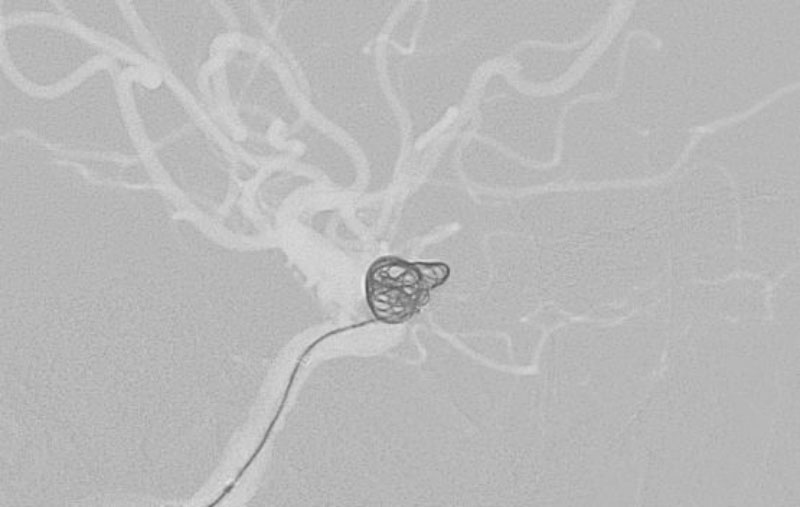

No.1596 手術中